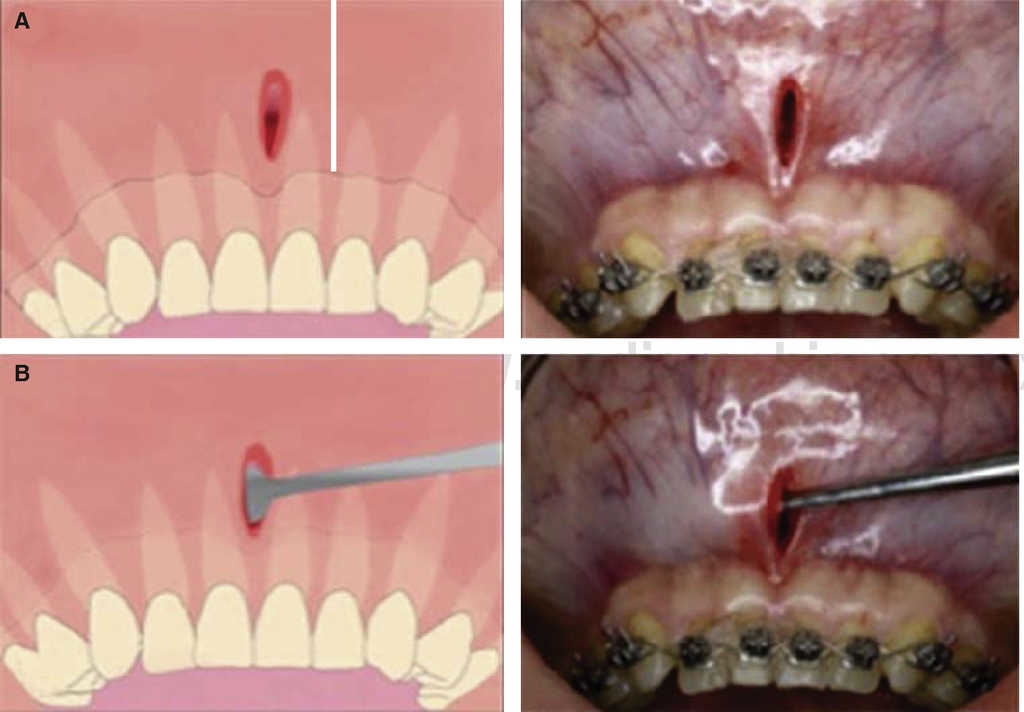

Piezocision technique1 (Dibart 2009)

In 2009 Dibart published a trans-mucosal corticotomy technique called piezocision. It is considered less invasive than the others while providing the same results. It decreases orthodontic treatment time in patients with reduced or intact periodontium, and achieves better results with less aggressive procedures.

In this surgical technique, vertical mini-incisions are performed with a number 15 scalpel micro-blade in vestibular inter-radicular spaces located from the base of the papilla, after this, trans-mucosal corticotomies are performed through previously executed incisions, at a 2 to 3 mm depth. It is not necessary to suture unless there was previous tunnel-building for bone implant placement. Orthodontic forces are applied every 14 days (Figure 14).

The advantage of this technique is that it is minimally traumatic, therefore post-surgical presence of pain, inflammation and ecchymosis is infrequent, since no full-thickness flap was previously raised1 2 and surgical time was short. This technique decreases damage to osteocytes and allows bone cell survival.1 One of the most important advantages of this technique is that the use of electrical scalpel, due to its micro-vibration, allows selective cutting of mineralized structures without damaging soft tissues. This is due to ultrasonic vibrations of 29 kHz frequency and 60/200 Hz range. Micro-metric vibration guarantees precise cutting (Figure 15).1 This technique suffers the disadvantage of allowing poor visibility, unavoidably requiring electrical scalpel use, and diffi culties inherent to control bone graft.2